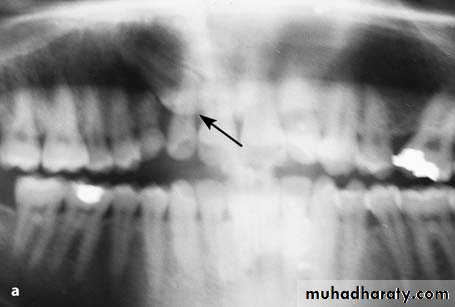

Radiograph showing impacted maxillary canines. Right canine is located labially while left canine is located palatally

Extraction of Impacted Canine with Partial Bone ImpactionRadiograph showing an impacted maxillary canine with a labial localization